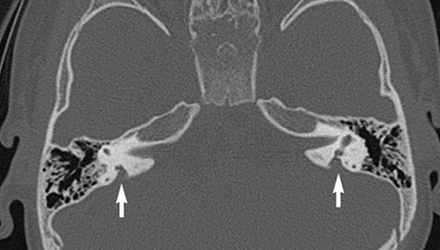

SLC26A4基因定位于人類染色體7q31,SLC26A4基因和大前庭導(dǎo)水管綜合征相關(guān)突變位點(diǎn)的發(fā)現(xiàn),證實(shí)SLC26A4是大前庭導(dǎo)水管綜合征的責(zé)任基因。

我們平時提到的“一巴掌打聾”、“一跤摔聾”其實(shí)都與SLC26A4基因突變有關(guān),絕大多數(shù)大前庭導(dǎo)水管綜合征都是SLC26A4基因突變?nèi)堑牡湣?/p>

SLC26A4基因編碼一種叫“Pendrin”的跨膜轉(zhuǎn)運(yùn)蛋白,在機(jī)體離子成分平衡的維持中發(fā)揮重要作用。

在內(nèi)耳,Pendrin表達(dá)于內(nèi)淋巴管、內(nèi)淋巴囊、橢圓囊、球囊等處,異變的蛋白將對這些結(jié)構(gòu)的正常生理功能產(chǎn)生影響,引發(fā)聽損。

SLC26A4基因突變導(dǎo)致的大前庭導(dǎo)水管綜合征的典型表現(xiàn)為兒童時期的聽力損失,90%的患者為雙側(cè)性,聽力損失程度不一,可表現(xiàn)為接近正常或重-極重度。

病程可為穩(wěn)定性、進(jìn)行性或波動性,聽力可逐步下降至全聾;跌倒、撞擊等行為或無外界影響都可能引發(fā)聽力的下降。